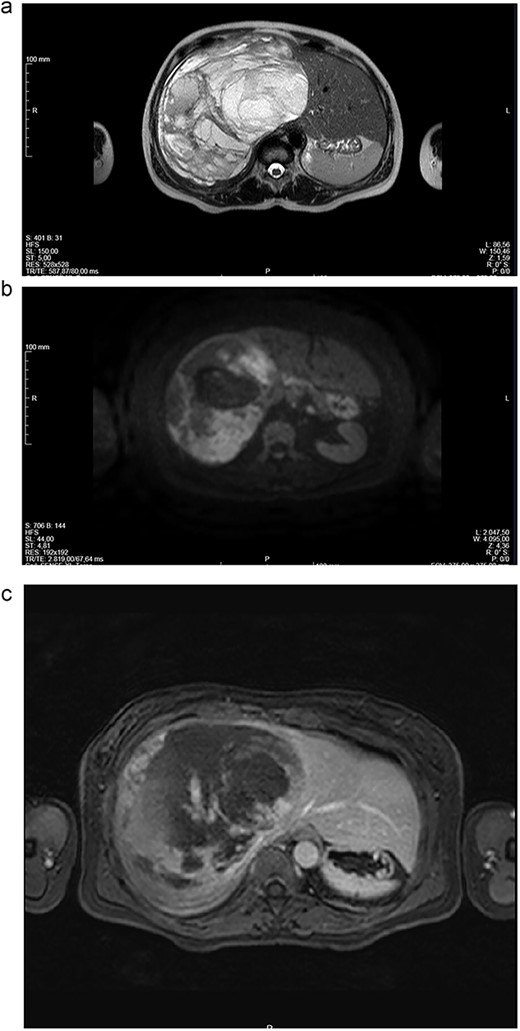

Abdominal CT (Fig. 1a and b) and MRI (Fig. 2a and b) showed a 18 × 12 × 20 cm3 lobulated cystic mass with thin enhancing septa in the right lobe of the liver with fluid levels suggesting atypical hemangioma. The right hepatic vein not dissociable to the tumor (Fig. 2c).

(a-c) Magnetic resonance imaging (MRI) scans of a woman aged 49 years with undifferentiated embryonal sarcoma of the liver. Liver of increased dimensions, due to the presence of a voluminous oval mass and well-defined limits occupying the entire right lobe. Heterogeneous mass with enhanced thin septa in the right lobe of the liver with fluid levels suggestive of atypical hemangioma. The right hepatic vein not dissociable to the tumor.